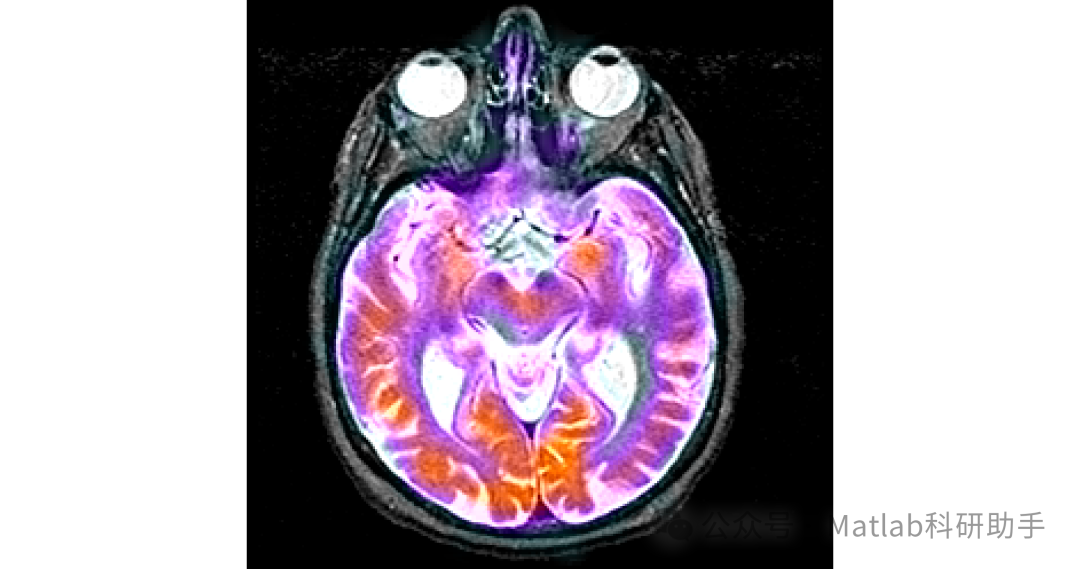

在现代医学诊断领域,医学影像技术扮演着不可或缺的角色。不同模态的医学图像能够提供人体组织和器官的不同信息,例如 CT 图像具有较高的空间分辨率,能够清晰地显示骨骼等高密度组织的结构;MRI 图像则对软组织的分辨能力较强,可准确呈现脑部、肝脏等软组织的病变情况。然而,单一模态的医学图像往往存在信息局限性,难以全面反映人体的生理和病理状态。

多模态医学图像融合技术应运而生,其旨在将不同模态医学图像中的有用信息进行整合,生成一幅包含更丰富、更全面信息的融合图像,为医生的诊断和治疗方案制定提供更有力的支持。例如,在肿瘤诊断中,将 PET 图像(可显示肿瘤代谢活性)与 CT 图像(可显示肿瘤位置和形态)融合,能够帮助医生更准确地确定肿瘤的范围和性质,从而制定更精准的治疗计划。

当前,多模态医学图像融合技术已成为医学图像处理领域的研究热点之一。但在实际应用中,现有融合方法仍存在一些问题,如融合图像可能出现细节丢失、边缘模糊、伪影等现象,影响了图像的质量和诊断价值。因此,研究更加有效的多模态医学图像融合方法具有重要的理论意义和实际应用价值。

本文针对多模态医学图像融合中存在的细节丢失、边缘模糊等问题,提出了一种基于联合双边滤波和局部梯度能量的多模态医学图像融合方法。通过对源图像进行联合双边滤波预处理,有效地去除了图像噪声,保留了图像的边缘和细节信息;利用局部梯度能量作为融合决策依据,确保了融合图像能够保留更多的细节信息;最后通过直方图均衡化和边缘增强等后处理操作,进一步改善了融合图像的质量。

实验结果表明,该方法在主观评价和客观评价方面均优于传统的图像融合方法,能够生成高质量的多模态医学图像融合结果,为医生的诊断和治疗提供了更有力的支持。